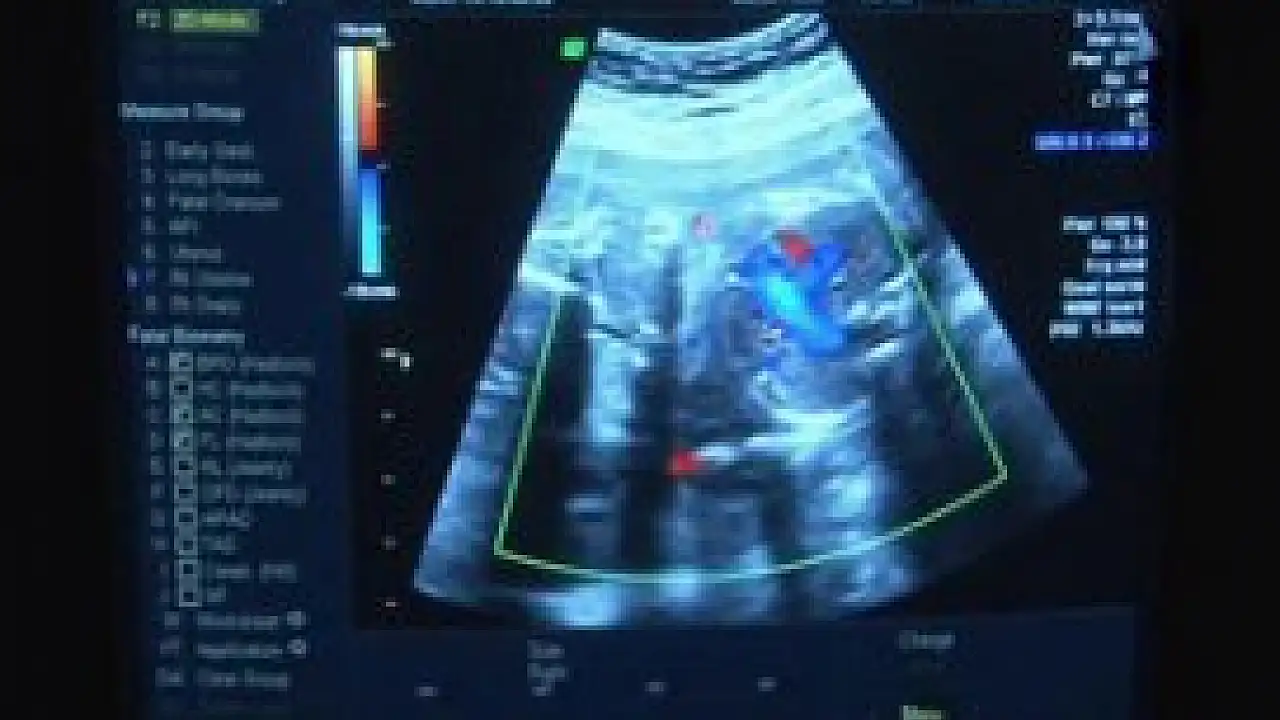

Kendilerine sevk edilen ve hamileliğinin 27'nci haftasında olan kadının yapılan kontrollerinde bebeğinin iki böbreğinde de sorun olduğunun tespit edildiğini dile getiren Acar, "Bebeğin böbreklerinde genişleme vardı. Böbrekte sıvı toplanmasının birçok sebebi olacağından detaylı inceleme yaptık. Böbreklerden çıkan kanallarda darlık vardı. Bu durum idrar torbasının geçişini zorluyordu'' dedi.

"Böbreklerin ikisine de müdahale ettik. Operasyon öncesi bebeğin etrafındaki boşluğa sıvı verdik. Etrafını görünür duruma getirdikten sonra böbreğe ulaştık. Bebeğin sağ böbreğine 8-10 santimlik şant yerleştirdik. Şantın bir ucu böbreğin içerisinde kaldı. Rahmin etrafındaki boşlukta böbrekten gelen idrarı biriktirip, bebeğin suyunu oluşturduk. Bu operasyon yapılmasaydı çocuğun yaşaması mümkün görülmüyordu. Bebeğin, böbrek yetmezliğine gitmesini önlemiş olduk. Çocuk doğduktan sonra dar olan böbrek ile idrar yolları arasındaki kanalın açılma işlemi yapılacak.''